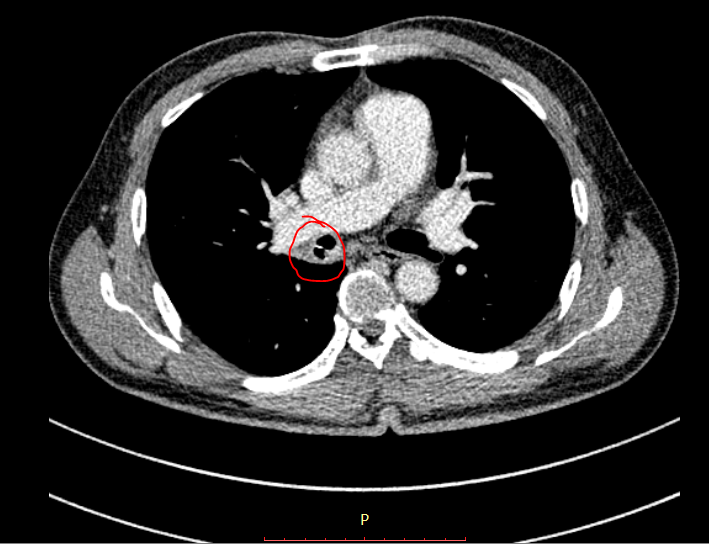

Tại đây, bệnh nhân được bác sĩ chỉ định chụp CT để truy tìm nguyên nhân. Kết quả ghi nhận vùng ở phế quản phải, nằm ở vị trí sát động mạch phổi có dị vật lạ không rõ bản chất, kèm viêm xung huyết quanh dị vật.

| Xương cá nằm trong phế quản. |

Các bác sĩ nhận định đây là một trường hợp rất khó khăn để thực hiện nội soi để có thể gắp dị vật ra thành công. Vì nguy gây cơ tổn thương lên động mạch phổi phải rất cao do vị trí gần sát, dẫn đến xuất huyết, phải mổ mở lồng ngực để cầm máu, và có thể gây nguy hiểm đến tính mạng người bệnh.